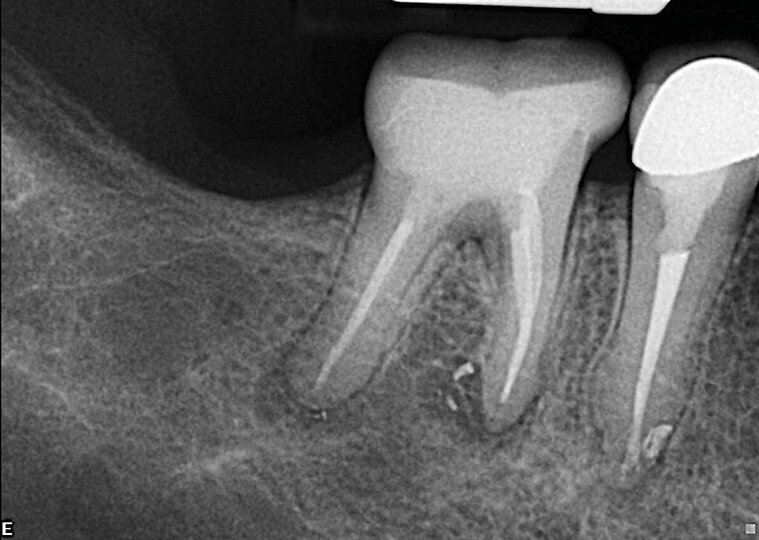

Slučaj 3 – Slika br. 9: Periapikalni kontrolni Rtg snimak odmah nakon tretmana

Slučaj 3 – Slika br. 10: Periapikalni kontrolni Rtg snimak nakon godinu dana od tretmana

Slučaj 3 – Slika br. 11: Periapikalni kontrolni Rtg snimak 18 meseci nakon tretmana

Poslednji slučaj o kome bih želeo da govorim u ovom članku, jedan je od najizazovnijih tretmana. Pacijentkinja je upućena iz inostranstva na remont gornjeg molara jer je insistirala na spasavanju zuba. Na malom rendgenskom snimku (Slika br. 6) sam jasno video da imamo separisan instrument u mezijalnom korenu, ali je anatomija bila veoma sumnjiva. Pacijentkinja mi je dala CD sa CBCT urađenim za nju, i gledajući različite delove , mada bih više voleo veću rezoluciju snimka (Slika br. 7), primetio sam 3 različita izlaza za mezijalni koren sa veoma neobičnom anatomijom. Proučavajući ovaj slučaj primetio sam i grananje na palatinalnom korenu u apikalnoj oblasti. Objasnio sam pacijentkinji da ću dati sve od sebe da joj spasem zub. Koristio sam istu sekvenca turpija Traverse i Zenflex u distalnom i palatalnom kanalu korena zuba do pune radne dužine, a kod mezijalnog korena sam dostigao do zalomlejnog instrumenta i prešao na veoma delikatan zadatak njegovog zaobilaženja i obrade ovog veoma složenog sistema korenskih kanala. Slika br. 8 prikazuje neposrednu postoperativnu i 3D obturaciju mezijalnog kompleksa, kao i palatinalno grananje. Slike br. 9 i 10 su nakon 12 i 18 meseci od tretmana gde se vidi dobro zarastanje i svaki put kada uzmem da pogledam iz drugačijeg ugla vidim složenost mezijalnog korena.